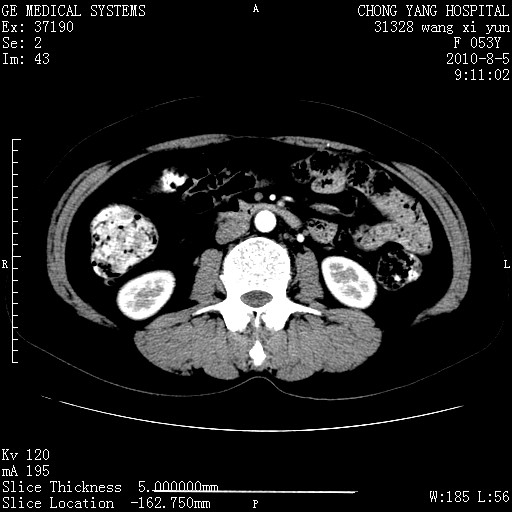

标题: CT28214:F41Y 血尿二十天,建议盆腔平扫加增强。

1)考虑肝左叶胆管细胞癌。2)脂肪肝。